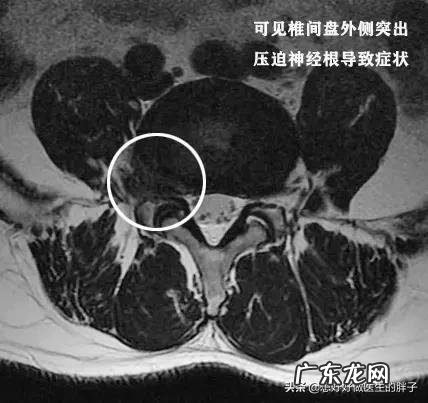

这是本人的一个患者,他本身就有腰椎间盘突出,但是不重,后来由于错误的搬动重物以后诱发剧烈的腰痛,不能正常睡觉,只能坐着才能减轻腰部以及肢体的疼痛、和麻木,后来给与其进行了椎管麻醉以后,才能平卧进行核磁,当时显示椎间盘突出属于侧方突出,压迫到了神经,单纯的看检查肯定是手术适应症 。

但是给予患者进行了椎管麻醉以后,患者的疼痛明显减轻了,连续观察了5~10天,患者已经可以正常的行走了,而且一个劲的吵着要上班,后来经过劝说才复查了核磁,结果发现患者的椎间盘突出已经达到了脱出的程度,复杂的核磁上,我们看脱出的髓核已经导致了椎管出现了明显的狭窄,如此严重的情况单纯看片子是手术适应症,但是患者却没有表现出来任何需要手术的症状,所以还是保守zhi疗了,最近一次随访是一个月前……患者很好!